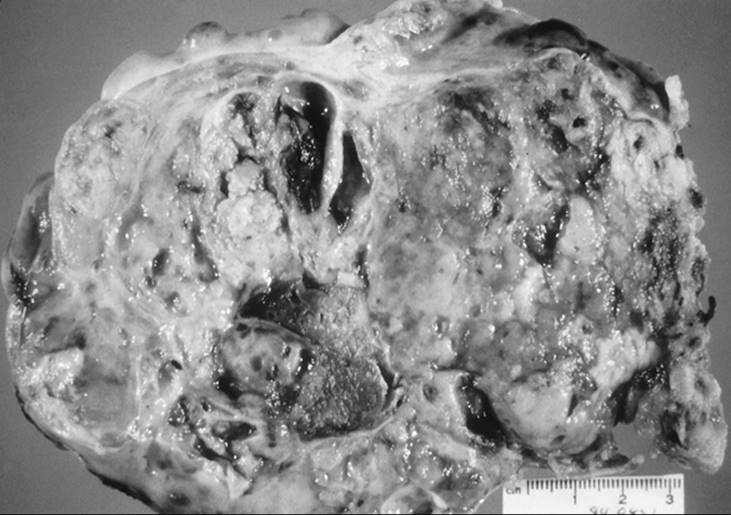

Adnexal masses in the young women may also be of germ cell origin. This is a special clinical scenario in that these neoplasms occur exclusively in young women. The main complaints include abdominal pain, with a pelvic mass found during examination. Some patients have acute abdominal pain resulting from torsion or rupture and hemorrhage of these masses. When evaluating a patient whose condition is not acute, the radiologic image usually reflects a solid mass with some cystic changes. The most common germ cell ovarian tumor is a dysgerminoma (Fig. 56.6). This is also the most common ovarian malignancy for young and pregnant women. This germ cell tumor is unusual in that it has a high incidence of bilaterality. Should a solid tumor be found and a germ cell tumor suspected, α-fetoprotein, human chorionic gonadotropin, and LBH levels may be drawn preoperatively, although none of these is necessarily predictive of finding a germ cell tumor. During surgery, given that most of these patients have not completed childbearing and that germ cells tumors most often are confined to the ovary, a conservative approach such as unilateral adnexectomy can be performed. Routine biopsy of the contralateral ovary in the case of a dysgerminoma is not recommended, even though the bilaterality rate is higher than with other germ cell tumors.

FIG. 56.6. Dysgerminoma in a 17-year-old girl.